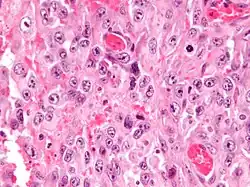

Intermed. mag. -

High mag. -

Histologically, epithelioid sarcoma forms nodules with central necrosis surrounded by bland, polygonal cells with eosinophilic cytoplasm and peripheral spindling.[3] Epithelioid sarcomas typically express vimentin, cytokeratins, epithelial membrane antigen, and CD34, whereas they are usually negative for S100, desmin, and FLI1 (FLI-1).[3] They characteristically lack the protein INI1 (see below). Epithelioid sarcomas typically stain positive for CA125.[4]